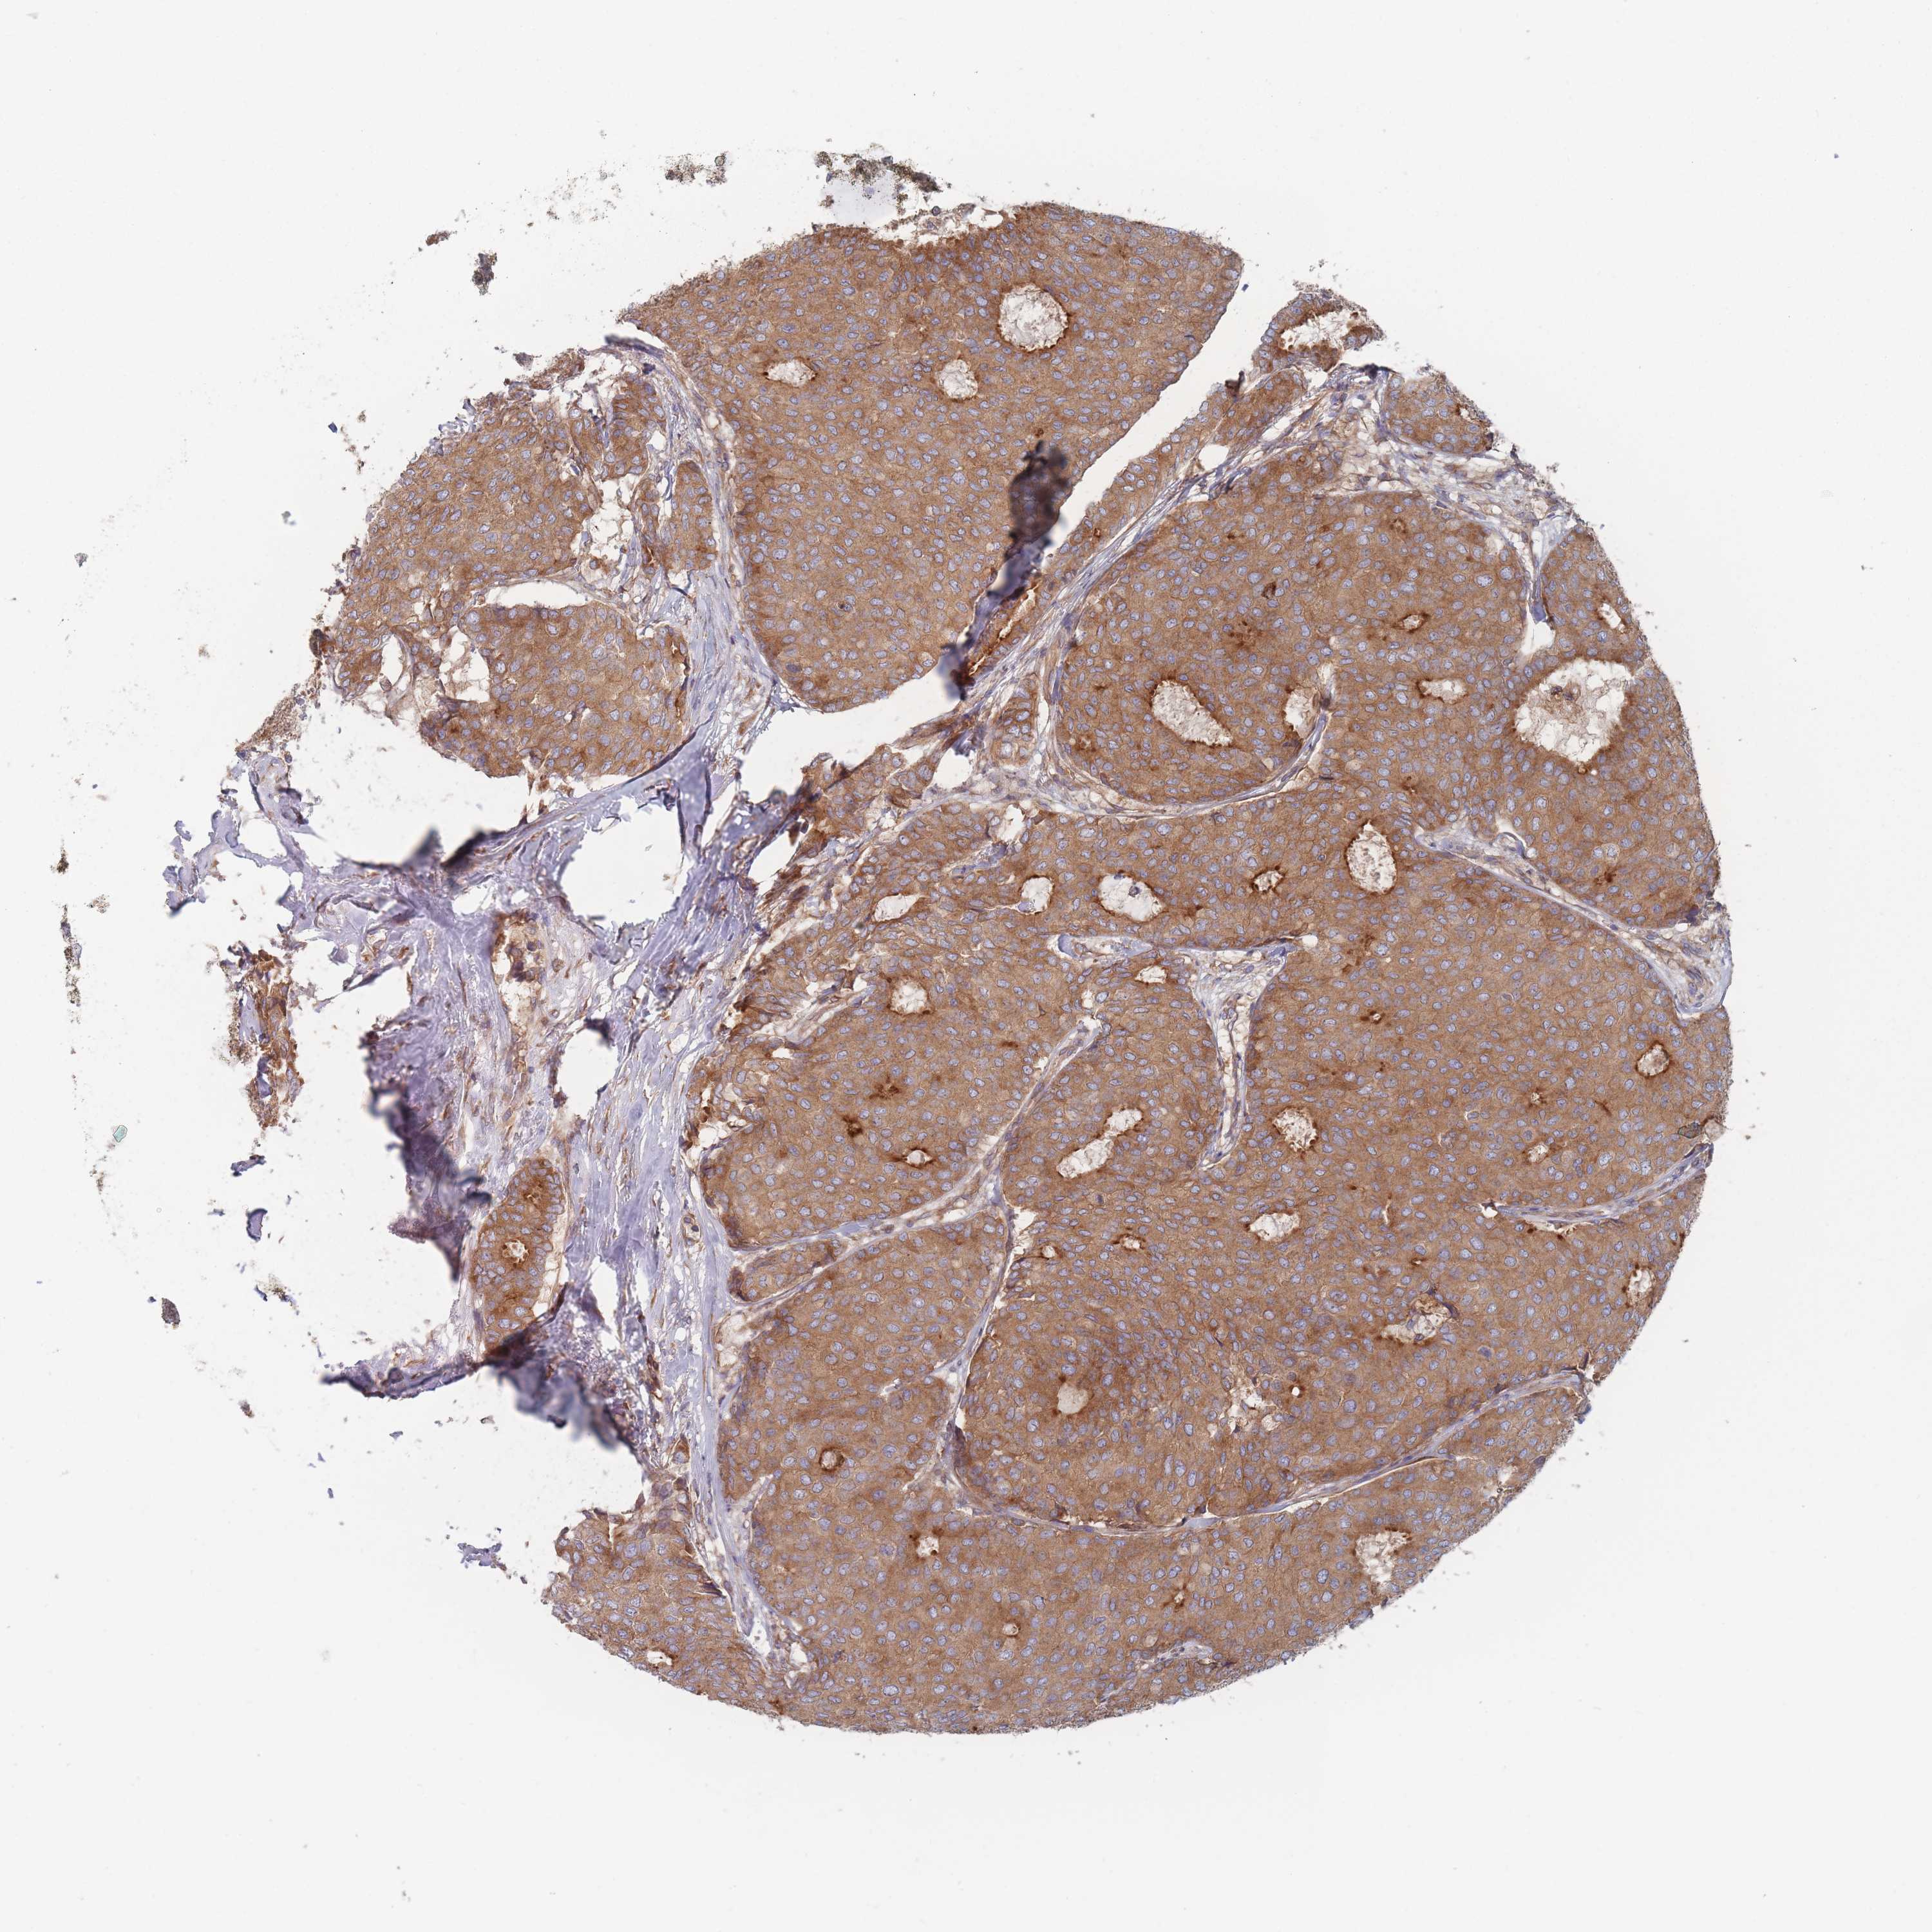

CANCER BREAST CANCER Show tissue menu

BRCA TCGA BRCA VALIDATION PROTEIN EXPRESSION